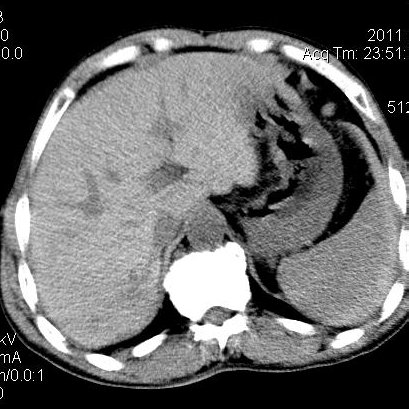

肝左叶发育异常

男性,55岁,骑摩托车摔倒后入院,自述右上腹疼痛

[backcolor=#FF0000]第一次诊断的时候也是这么肯定,可是床旁超声检查并没有发现明显异常,而且患者的一般症状都良好。还好临床只是保守治疗,没有立即手术,第二次复查的时候没有一点变化,又做了MRI检查,没有血肿,

这是一例肝左叶发育异常的,很个性吧~[/backcolor]